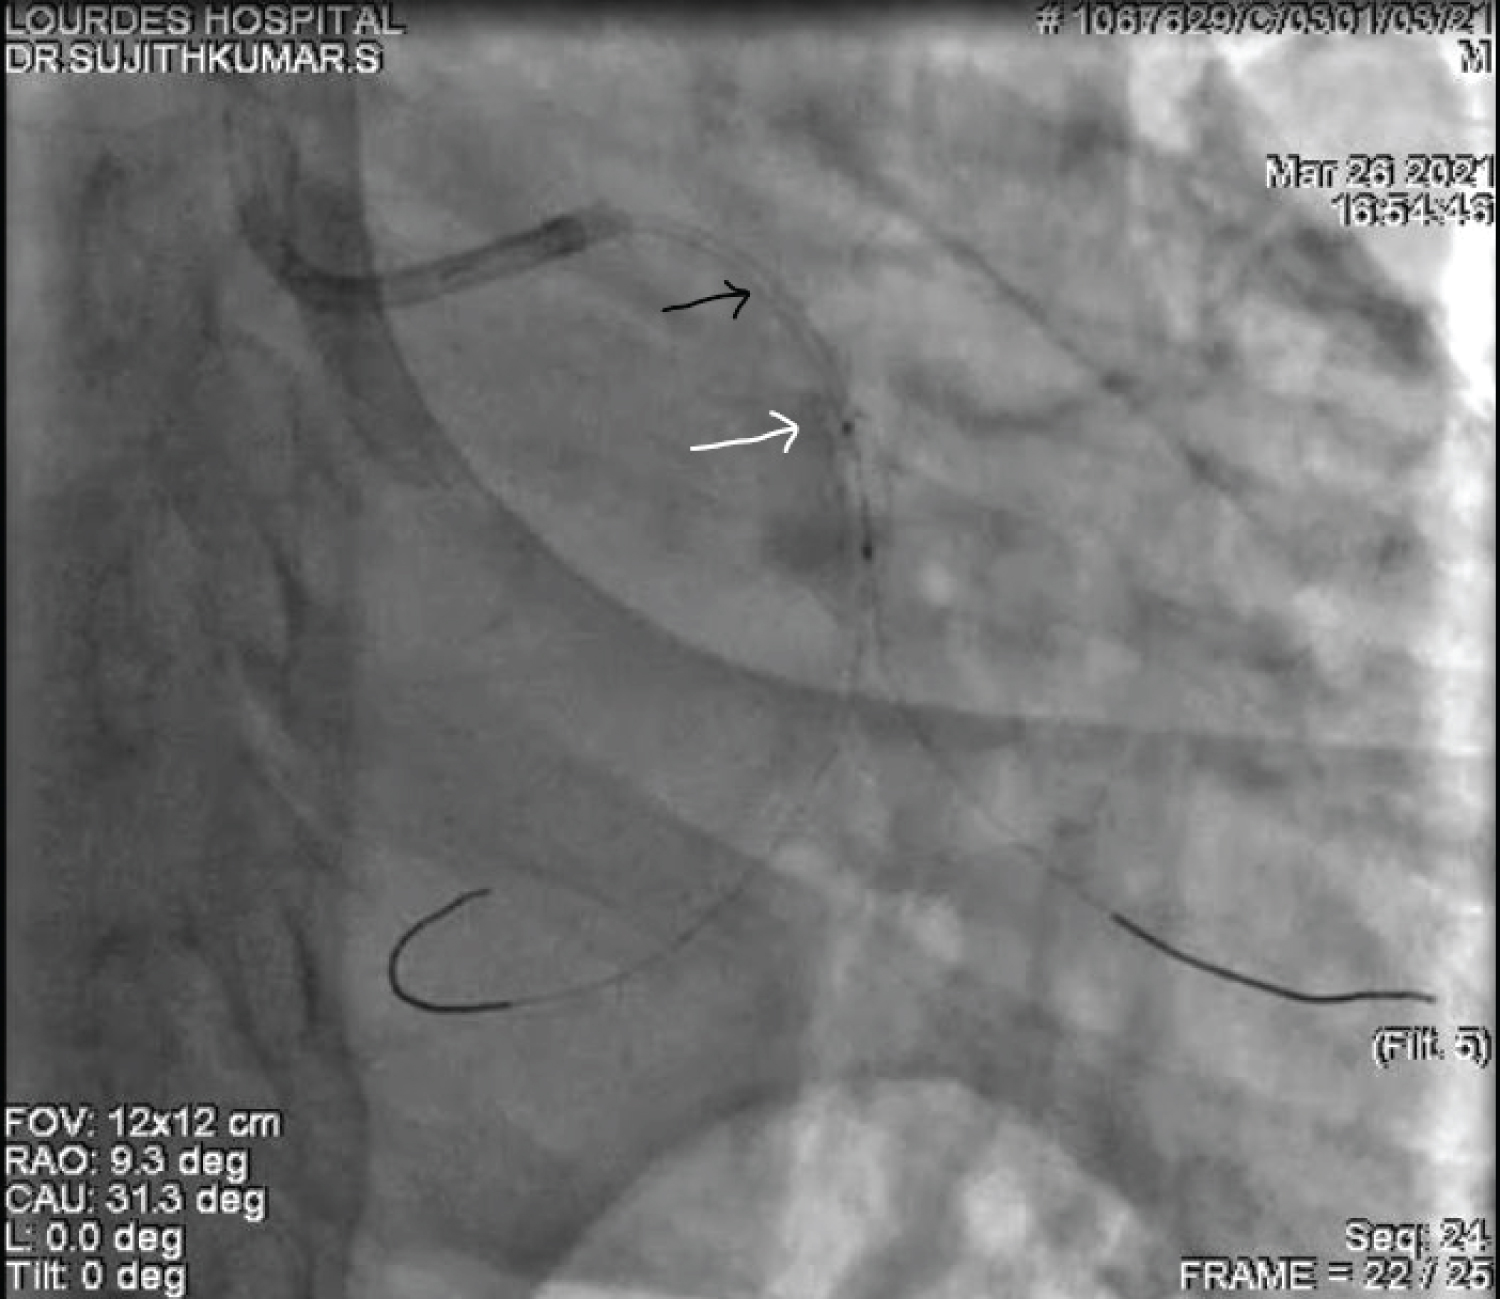

A 60-year-old gentleman was referred to our care with a diagnosis of Inferior Wall Myocardial Infarction, after receiving thrombolytic therapy at a local hospital. ECG, at admission, showed good ST resolution. He was taken up for elective coronary angiogram and revascularization. Coronary angiogram revealed a critical stenosis of dominant Left Circumflex artery (LCX) at Obtuse Marginal artery (OM2) (medina 1,0,1) with TIMI II flow distally (Figure 1 and Video 1). He underwent angioplasty and stenting with a single stent strategy. The LCX was predilated and was stented with a 3 × 24 mm Biomime stent at 14 atmospheres (Figure 2, Figure 3, Figure 4, Video 2 and Video 3). The OM2 was rewired and a dilatation of the ostial lesion of OM2 and kissing balloon inflation was done with excellent result. It was decided to do proximal optimization (POT) to the proximal stent with a 3.25 × 8 mm non-compliant (NC) balloon. But there was difficulty in tracking the balloon down into the stent and fluoroscopy showed a deformation of the proximal edge of the stent which was confirmed by the Stent Viz technology (Figure 5, Figure 6, Figure 7, Video 2 and Video 3). The same NC balloon was then used to post-dilate the stent and the proximal part of the stent was covered with another 3.5 × 13 mm biomime stent with excellent result (Figure 8). After 4 months follow up, the patient is asymptomatic and on dual antiplatelets.

Figure 6: Coronary angiogram in RAO Caudal projection after the rewiring of OM and the passage of post dilatation balloon into the stent (the black arrow denotes the initial position of the stent and the white arrow shows the deformed and displaced proximal end of stent). View Figure 6